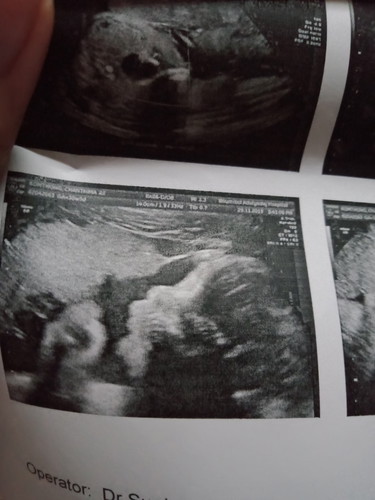

น้องเปิดหน้า

ตลอดเวลาที่ที่ไปอัลตราซาวด์ 3 ครั้งน้องปิดหน้าตลอด พอมาเมื่อวานครั้งที่ 4 เราเห็นชัดมากว่าน้องปิดหน้าก็อดขำกับแฟนไม่ได้ อะไรจะขี้อายขนาดนั้น 55555 หมอเลยแกล้งปลุกน้อง สักแปปน้องตื่นรียเอามือออก ผลที่ได้ออกมาก็เป็นแบบนี้เลยค่ะ 55555 ปล. 3 ครั้งแรกหมอ ผญ ครั้งที่ 4 หมอ ผช สงสัยน้องเขินหมอ 55555